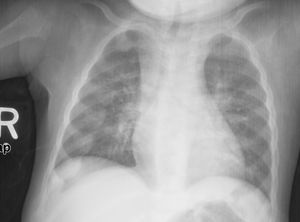

X선 또는 방사선 사진은 구루병의 고전적인 양상(O다리, 변형된 가슴)을 보여준다. 두개골의 변화도 발생하여 "사각형 머리" 모양인 "사각두"가 나타난다.[18] 이러한 변형은 치료하지 않으면 성인기에도 지속된다. 장기적인 결과로는 장골의 영구적인 만곡 또는 변형과 굽은 등이 있다.[19]

- 방사선 사진에서는 일반적으로 석회화되지 않은 골기질로 인해 일시적 석회화 영역이 넓어지는 것을 보여준다. 컵 모양 변형, 섬유화, 골단의 벌어짐은 성장과 지속적인 체중 부하와 함께 나타난다.[47] 이러한 변화는 상완골 근위부, 요골 원위부, 대퇴골 원위부, 경골 근위부와 원위부를 포함한 빠른 성장 부위에서 주로 관찰된다. 따라서 구루병에 대한 골격 전반 검사는 무릎, 손목 및 발목의 전후 방사선 사진으로 수행할 수 있다.[47]